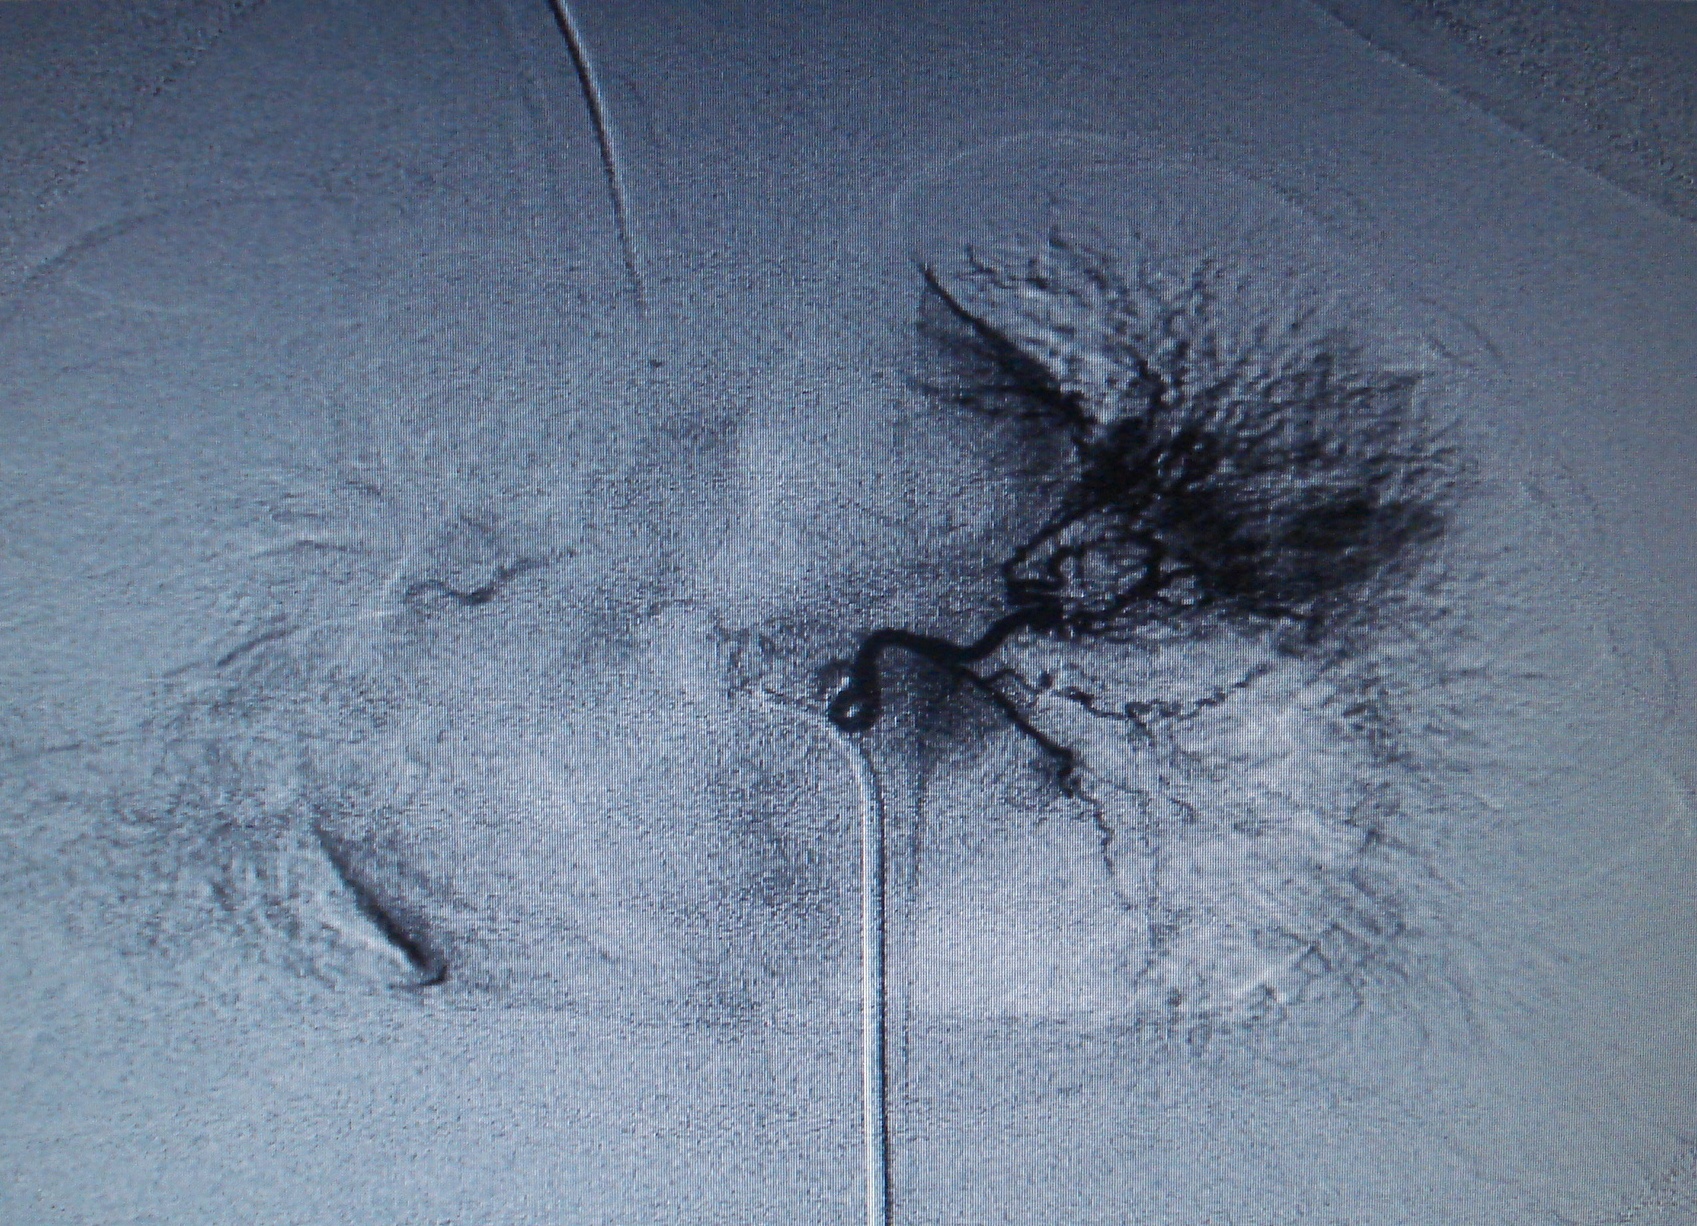

Paciente de 1 año y seis meses, con antecedentes de infecciones respiratorias recurrentes localizadas y hemoptisis. Mediante angiografía de la arteria pulmonar y de las ramas bronquiales de la aorta descendente se diagnostica estenosis de venas pumonares con colaterales aortopulmonares.La revista no retiene los derechos de reproducción (copyright) por lo que los autores pueden volver a publicar sus trabajos con la sola mención a la fuente original de publicación.